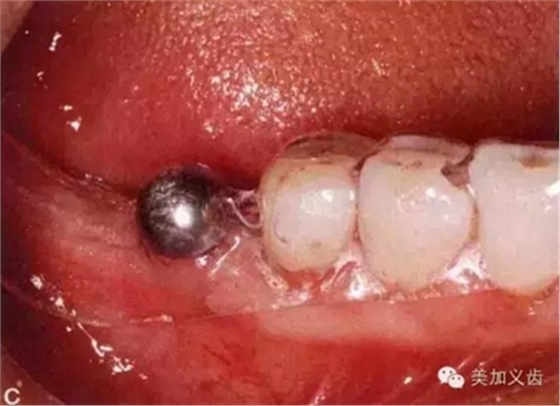

拍片時怎么把小剛球固定在口內(nèi)?有的牙醫(yī)用紅蠟把它固定在鄰牙上,這是一種比較玩火的做法,一旦掉了怎么辦?重新拍?一旦患者把小剛球咽到肚子了怎么辦?讓患者賠你小鋼球?我一定是在開玩笑,呵呵,患者不讓你賠錢就不錯了。

別嫌麻煩,給患者術前取個模型,然后通過壓膜來制作放射導板,這樣小剛球就固定在導板里了,別說你的診所沒有壓膜機哈......

然后將導板放到口內(nèi)進行拍攝就可以了。